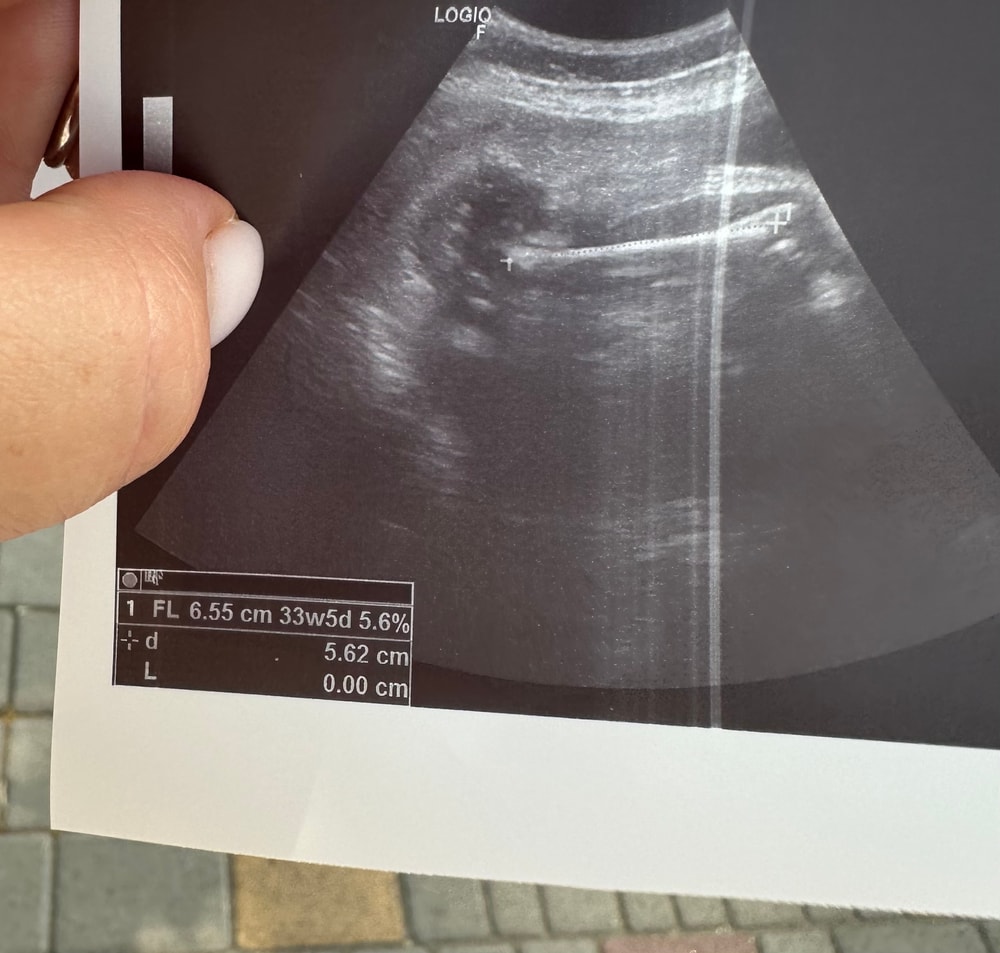

Результаты УЗИНа снимке узи бедренной кости. Значение соответствует 6.55 см, но ниже написано +d 5.62 cm. Почему отличаются?( Месяц назад бедро было 59, то есть 56 никак не может быть. Что это за значение в таком случае?

В фетометрии (т.е. узи плода) маленькая буква "d" с таким крестиком обозначает диаметр и часто встречается в сочетании с другими буквами для обозначения различных параметров, таких как BPD или FL.

FL (Femur length) - это как раз длина бедренной кости, в вашем случае 6.55, а d тут показывает параметр диаметра измерения в одном из участков, скорее всего, он никакого значения тут у вас не имеет, и к показателю длины точно никак не относится

LilinePotter, d - дистанция. Уже нашла ответ. Когда аппарат переводят в режим того или иного параметра (в моем случае - бедренная кость), там идет алгоритм расчета. То есть d корректирует аппарат с учетом угла наклона и тд. Просто обычно пишут только значение FL, а мне вручили с этим дурацким d.

LilinePotter, диаметр тоже так обозначают, но там должна быть окружность) в линейных замерах просто дистанция. Короче да, много нюансов, вроде как разобралась, как считает, но все равно большая разница вышла.

Ирина, так мне написали что бедро 65мм, и на снимке есть этот параметр. Но ниже написано что расстояние между точками 56. Я пытаюсь в этом разобраться.

Julia, Там по идеи не крайние места оттыканы, а только прямая часть, а так мне снимки никогда не отдавали)